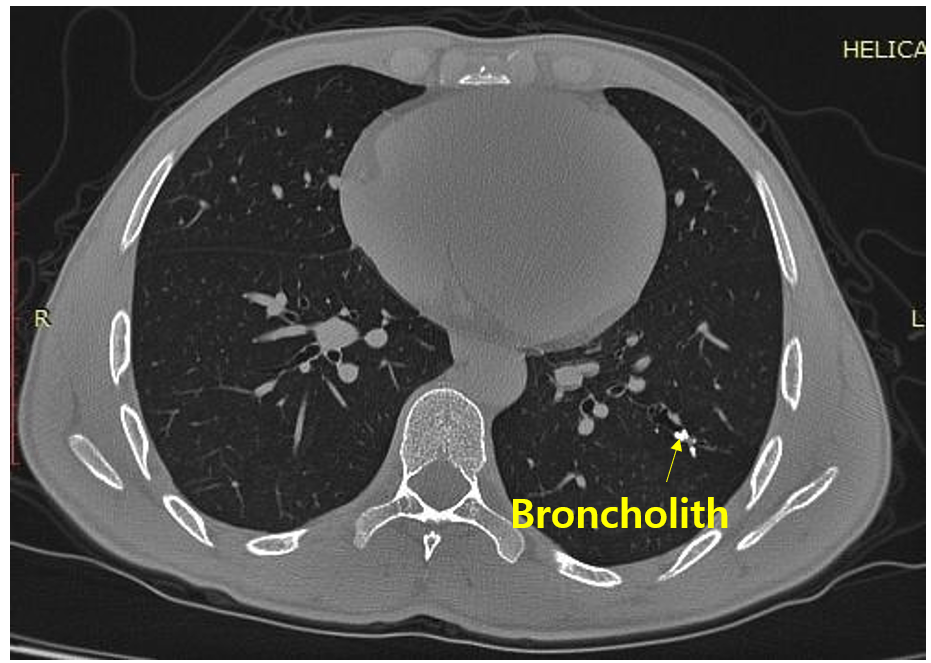

2. 기관지결석(broncholithiasis)

1) 원인

(1) 석회화된 LN이 bronchial lumen 내부로 이동함: 결핵, 진균 감염, 규폐증(silicosis) 등

(2) 흡인된 이물, 양성 종양 등이 석회화됨

2) 임상양상

(1) 주호소: 기침

(2) 기타 증상 및 징후: 호흡곤란/발열(폐쇄성 폐렴), 객혈

3) 검사소견: CT - bronchus 내부에 very high-attenuating mass

4) 치료

(1) 경과관찰: 증상이 없거나 경할 때

(2) 기관지내시경 or 수술적 제거: 증상이 심할 때